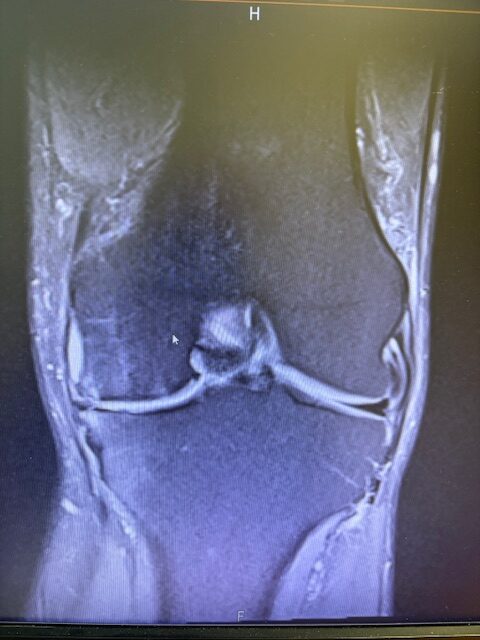

Ο ακτινολογικός έλεγχος (ακτινογραφίες/μαγνητική τομογραφία) ανέδειξε προχωρημένη οστεοαρθρίτιδα του έσω κονδύλου, με πλήρη διατήρηση του έξω διαμερίσματος και της επιγονατιδομηριαίας άρθρωσης. Με βάση αυτά τα ευρήματα, ο ασθενής ήταν ιδανικός υποψήφιος για μερική (μονοκονδυλική) αρθροπλαστική γόνατος.